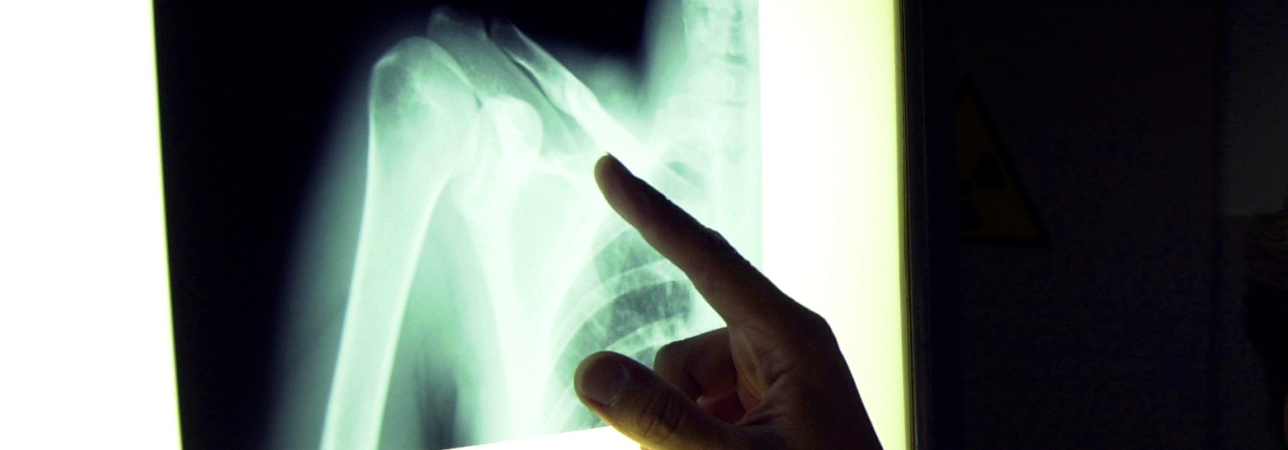

Nei primi giorni di maggio, alla Clinica Ars Medica di Gravesano si è svolta una prima assoluta a livello cantonale, l’impianto di una protesi inversa su misura (custom made) alla spalla destra di una signora di 84 anni. Un lavoro di concerto tra il dottor Francesco Marbach, specialista in Chirurgia ortopedica e traumatologia dell’apparato locomotore alla clinica di Gravesano, e la LimaCorporate con il suo team ProMade di San Daniele, azienda italiana leader nella produzione di impianti ortopedici. Con lo specialista abbiamo ripercorso le tappe di questo intervento.